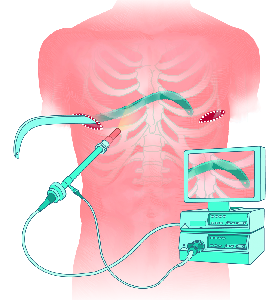

Detailreiche Fotografien aus der medizinischen Praxis ergänzen die Texte; moderne, genaue,

wissenschaftliche Zeichnungen geben Einblick in die Anatomie und die Funktion der Lunge und

anderer Organe.